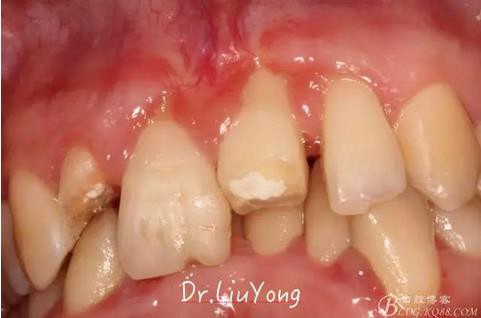

術(shù)后兩周復(fù)查,牙齦紅腫明顯好轉(zhuǎn),探診不出血,但是此時(shí)A1唇側(cè)牙齦角形退縮1.5mm,B1唇側(cè)牙齦退縮3.5mm,B1遠(yuǎn)中牙齦乳頭萎縮明顯,B2近中牙齦萎縮約1mm,且A1B1B2牙齦退縮處角化牙齦幾乎缺失,同時(shí)上唇系帶直接牽拉于B1齦緣?;颊邽楦咝€女性,露齦笑,由于存在前牙區(qū)牙齦的高度嚴(yán)重不對(duì)稱及前牙牙冠過(guò)長(zhǎng)的問(wèn)題,因此嘗試通過(guò)膜齦手術(shù)改善患牙牙齦退縮。通過(guò)術(shù)前分析,A1唇側(cè)牙齦退縮屬于Miller分類第一類, B1唇側(cè)牙齦退縮屬于Miller分類第3類(B1遠(yuǎn)中牙齦乳頭為2類,Nordland and Tarnow分類法),B2唇側(cè)牙齦退縮屬于Miller分類第3類,由于擬采用冠向復(fù)位瓣的方式治療牙齦退縮,因此需要先行上唇系帶修整術(shù),解除上唇系帶帶來(lái)的過(guò)大牽引力。

系帶手術(shù)后兩周,進(jìn)行上頜前牙唇側(cè)的牙齦退縮的手術(shù)治療,由于局部附著齦缺如及牙齦厚度不足,因此同期進(jìn)行上皮下結(jié)締組織移植,解決附著齦及牙齦厚度不足的問(wèn)題。

術(shù)中,可見明顯的唇側(cè)骨開裂,如上圖